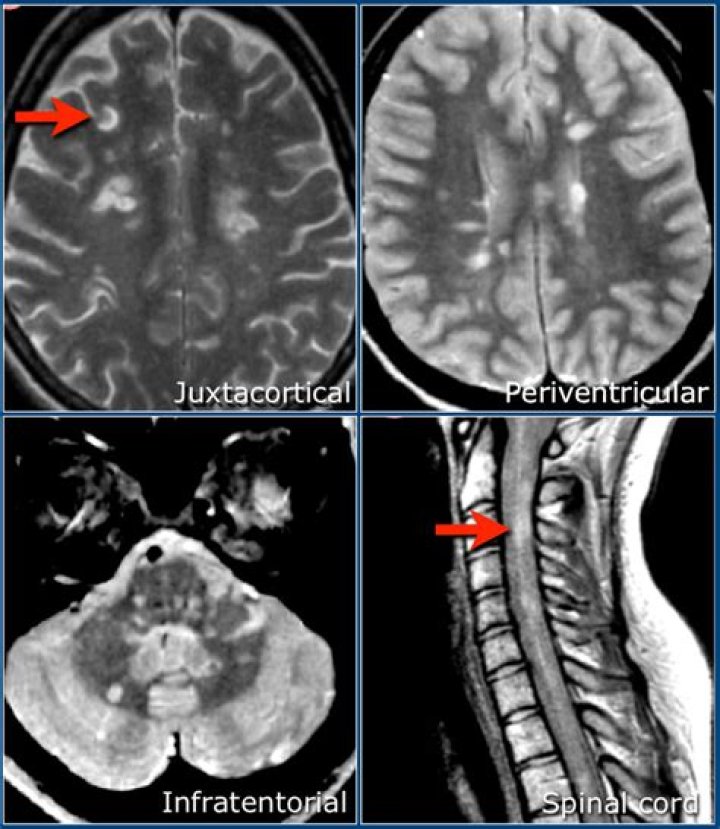

Under the McDonald Criteria (revised), an MS diagnosis is likely if myelin damage is disseminated in space, as seen in an MRI as: At least one T2 bright lesion in at least two or four CNS locations: the juxtacortical, perventricular and infratentorial areas of the brain, and the spinal cord.

A common type of MRI for MS is a T2-weighted scan, which detects all areas of myelin damage in the brain and spinal cord. We can now use a technique called FLAIR to make it easier to spot the lesions. Doctors will also use a contrast agent called gadolinium with a T1-weighted scan to focus on newer, active lesions.